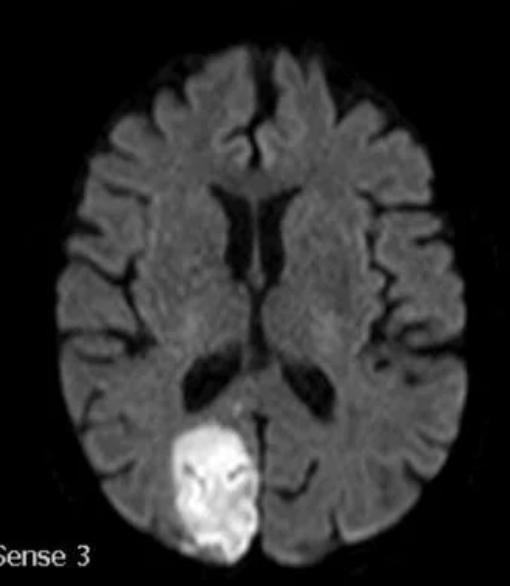

Supply areas of the cerebral arteries. A: axial slice; B: coronal slice. (1) Anterior cerebral artery, (2) middle cerebral artery, (3) posterior cerebral artery, (4) anterior choroidal artery, (5) lenticulostriate arteries.